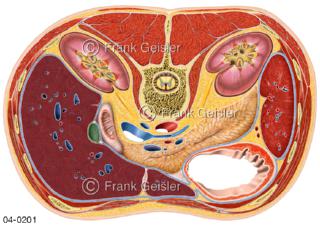

Bildergalerie Topografie Organe

Bilder zur topografischen Anatomie, die Lage der Organe und die Strukturen nach ihren räumlichen Lagebeziehungen zueinander, Übersicht der inneren Organe im Kopf und im Rumpf, Topografie der Organe im Brustraum (Thorax) und im Bauchraum (Abdomen)